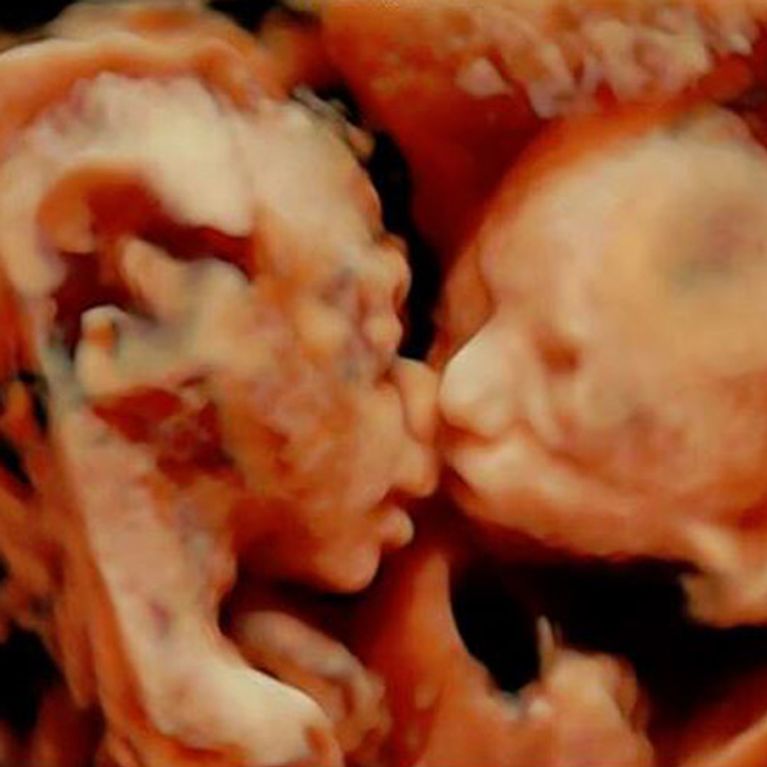

Kumar trug seit seiner Geburt einen Zwilling in sich Denn die Zwillinge nehmen schon ab der fünften Schwangerschaftswoche wahr, dass da noch jemand bei ihnen ist.

Sie hören den Herzschlag des Zwillings lauter als den der Mutter und teilen sich häufig sogar den gleichen Blutkreislauf. Dieses Bild zeigt ein ganz besonderes Zwillingspaar.

Tatsächlich: Zwillinge fangen schon in Mamas Bauch an, sich gegenseitig vorsichtig zu berühren. Nicht per Zufall oder als Reflex, sondern offenbar ganz zielgerichtet Das man mit Zwillingen im Bauch schon relativ früh während der Schwangerschaft nicht mehr auf dem Bauch schlafen kann, leuchtet ein.